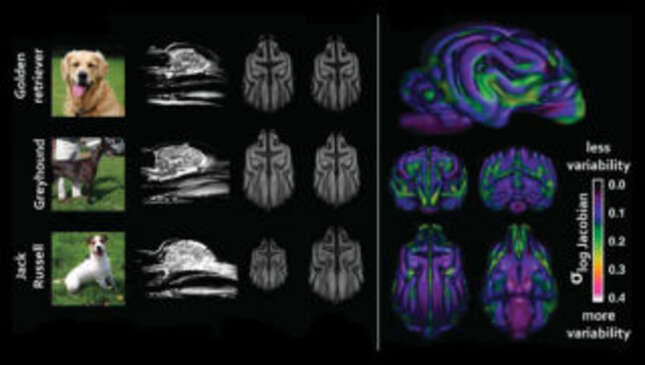

Kent le proporcionó a Hecht un tesoro de escáneres cerebrales tomados de machos y hembras buenos que se habían hecho una resonancia magnética pero que no tenían problemas neurológicos. Con estos escaneos, el equipo de Hecht pudo comparar de cerca los cerebros de 62 perros de raza pura de 33 razas diferentes. Lo que encontraron podría parecer obvio a primera vista, pero resalta cómo los perros con dueños se han convertido para la humanidad.

“Nuestro hallazgo básico es que las diferentes razas de perros tienen una anatomía cerebral diferente”, dijo Hecht a Gizmodo por teléfono. Los hallazgos del equipo fueron publicados el lunes en el Journal of Neuroscience.

“Esa fue mi primera reacción también: tienen cuerpos diferentes, por supuesto tienen cerebros diferentes. Pero realmente, nadie ha visto esto antes. Lo cual es algo sorprendente”, dijo Hecht. “Y entonces, lo que encontramos fue que las diferencias en la anatomía del cerebro van más allá de las diferencias en el tamaño del cuerpo, el tamaño del cerebro y la forma general de la cabeza. Y creemos que estas diferencias se explican por la cría selectiva de comportamientos”.

Un ejemplo, dijo Hecht, involucraba a perros criados para ser buenos rastreando visualmente animales como pájaros a través de un entorno, como los golden retrievers. Y cuando el equipo comparó a estos perros con otras razas, parecían tener diferencias clave en las regiones cerebrales relacionadas con la coordinación, el movimiento ocular y la navegación espacial, todo lo que necesitan para ser un buen rastreador.